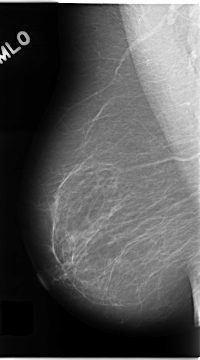

C_0138_1.RIGHT_MLO

RIGHT_CC LINES 4712 PIXELS_PER_LINE 2656 BITS_PER_PIXEL 12 RESOLUTION 50 NON_OVERLAY

RIGHT_MLO LINES 4680 PIXELS_PER_LINE 2600 BITS_PER_PIXEL 12 RESOLUTION 50 NON_OVERLAY